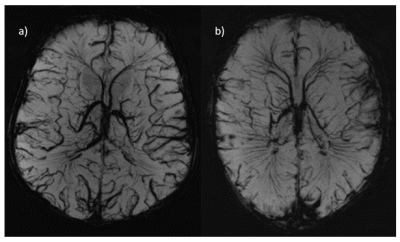

SWI at 7T allowed clear visualisation of the cerebral blood vessels as seen in Figure3. Two examples are shown, one in a participant with congenital cardiac anomalies (transposition of the great arteries) (Figure3b)), and another from a healthy control (Figure3a).

Figure 3: a) Cerebral vasculature as characterized by SWI in a) Healthy Control Infant and b) in a participant with transposition of the great arteries.